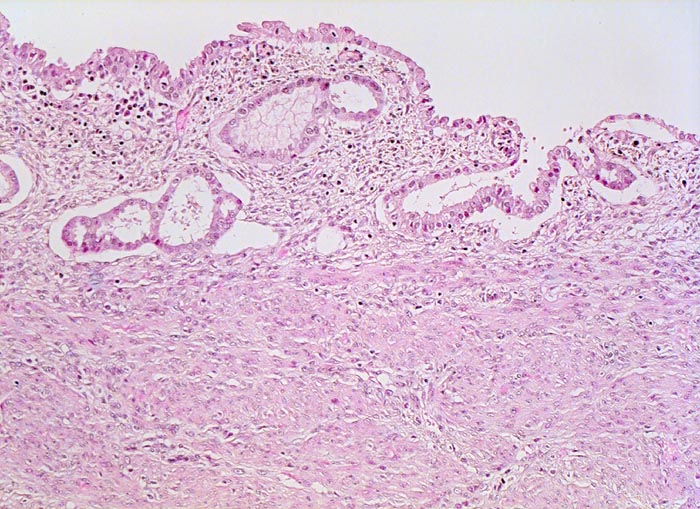

• Die rechte Seite des Uteruskavums wird ausgekleidet von flachem atrophem Endometrium. Im Cavum liegt ein Blutkoagel mit nekrotischem Detritus nach vorausgegangener diagnostischer Utersukurettage.

• Anmerkung: Typischerweise ist das endometrioide Karzinom des Uterus als Folge des ursächlichen Hyperöstrogenismus assoziiert mit einem hyperplastischen Endometrium (siehe Präparat 148). Im Kurspräparat erscheint hingegen das nicht-neoplastische Endometrium nach vorausgegangener Kurettage atroph. Atrophes Endometrium findet sich sonst charakteristischerweise neben serösen Endometriumkarzinomen postmenopausaler Patientinnen. Das sollte der Kliniker dem Pathologen mitteilen: